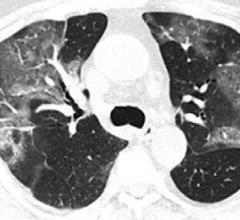

February 5, 2020 — In a special report published in the journal Radiology, researchers describe computed tomography (CT…